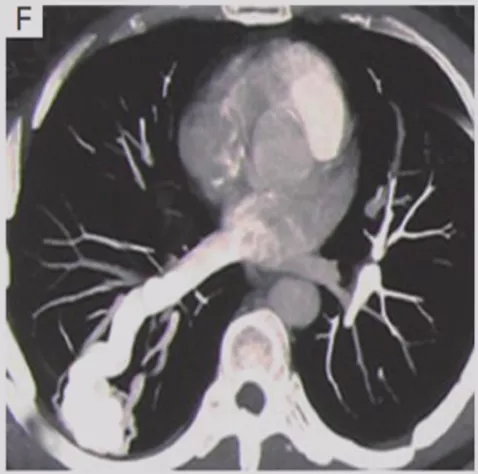

小细胞肺癌

小细胞肺癌以中央型多见,但是也有少数为周围型病灶。多为单个实性结节或肿块,可见分叶、毛刺、血管集束征、胸膜牵拉征。实际上我们很难从影像学上判断出小细胞肺癌的病理类型,往往是活检或者手术以后才能证实。如下图示,这属于I期的小细胞肺癌,进行手术的效果非常好。所以对于周围型小细胞肺癌,如果在结节很小的时候判断出来就做了手术,疗效非常好。我们知道小细胞肺癌是肺癌中治疗效果最差的,恶性程度是最高的。如果早期手术,仍然能够起到很好的效果。